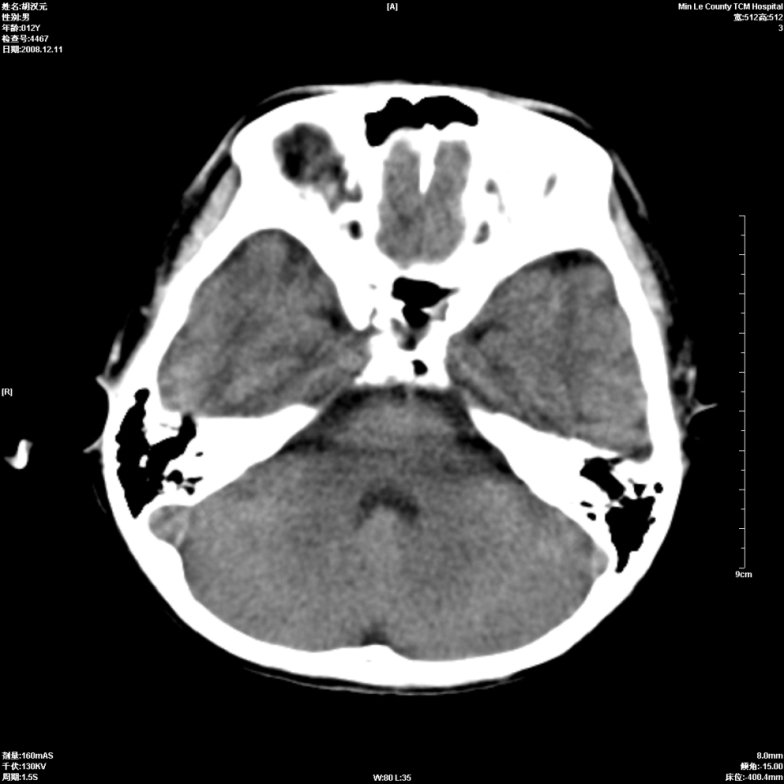

标题: PED1681:头疼发热约一周 [打印本页]

标题: PED1681:头疼发热约一周

颅脑未见确切异常。必要时进一步检查,如mri、脑脊液检查。

左侧基底节区腔梗?可以考虑吗?

两侧顶部近灰质处白质密度降低,是否炎性改变

颅脑ct轴位平扫颅内未见明确异常;建议必要时复查或行进一步检查。

两侧顶部近灰质处白质密度降低,建议mri